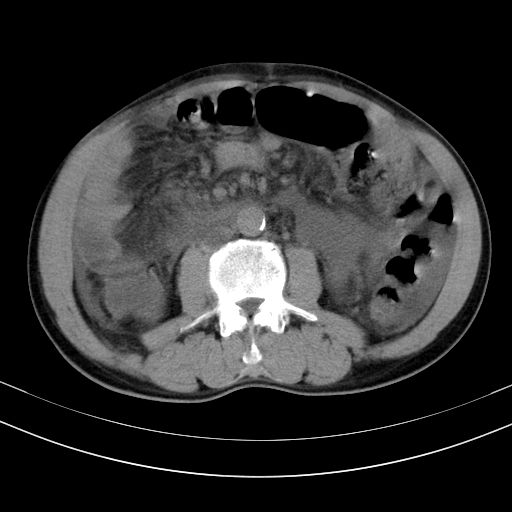

以下是引用随光逐影在2010-2-28 10:23:00的发言:[br]1)考虑肝癌;建议行ct增强扫描检查。2)肝硬化,脾大,腹水。3)慢性胆囊炎。

以下是引用dyqct在2010-2-28 16:44:00的发言:[br][quote]以下是引用随光逐影在2010-2-28 10:23:00的发言:[br]1)考虑肝癌;建议行ct增强扫描检查。2)肝硬化,脾大,腹水。3)慢性胆囊炎。